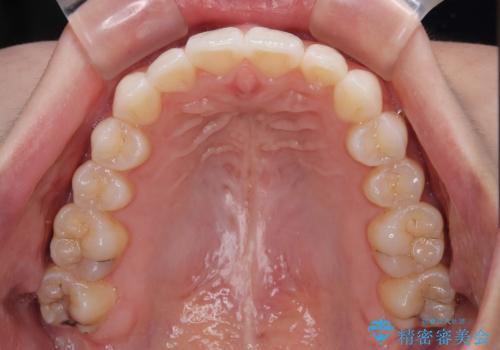

上下前歯の突出感とデコボコを気にして来院された患者様です。

インビザラインによる上下歯列の側方拡大と後方移動、必要に応じてIPR(歯と歯の間を削る)によりスペースの獲得により歯列を整えることとしました。

治療途中、出産や転居があり、2年ほど治療期間が長くなってしまいましたが、前歯の歯並びや飛び出した感覚を無事に改善させることができました。